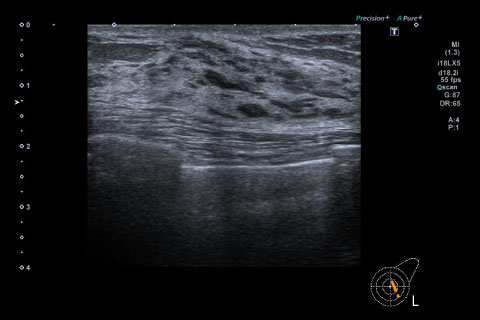

頚部超音波検査

この検査で、全身の動脈硬化の程度を現す指標を評価できます。さらに血流波形を得ることによって頭蓋内血管や大動脈での病変の推定も可能です。

動脈硬化の程度は、血管壁第1層と第2層の内中膜複合体(IMC)の厚さを計測し、評価します。

また、頸動脈血管腔のつまりや狭小化の観察、プラークの大きさ、形状、表面・内部の状態(硬さ)などを観察し、治療方針などを検討します。